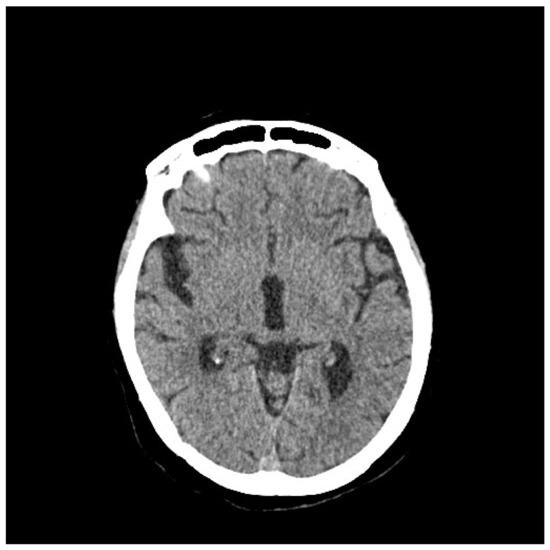

2. Case Presentation